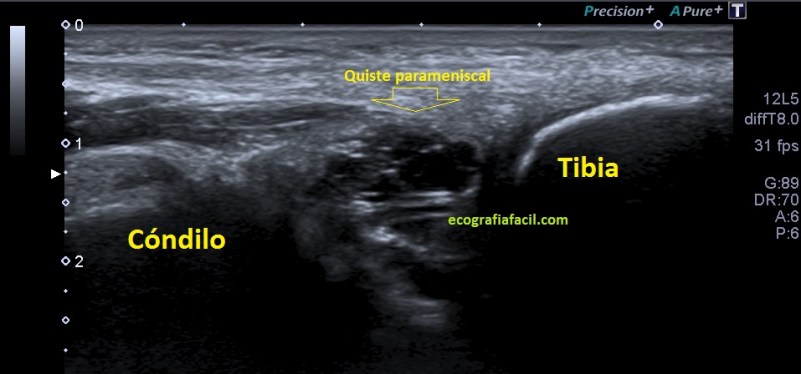

La presentación de éste era así:

5

Semiológicamente ves una ecoestructura anecoica con septos hiperecogénicos paralelos en alguna porción del quiste que no muestra vascularización. Este estaba en torno a los 2,5 cms, en el momento de la exploración.